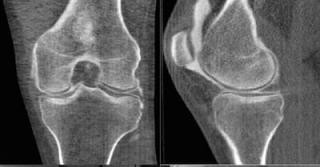

Рентгенография является основным методом диагностики гонартроза и позволяет определить:

• сужение суставной щели

• наличие остеофитов

• степень деформации сустава

КТ (компьютерная томография) назначается, когда необходимо:

• более точно оценить костные структуры

• выявить выраженные деформации сустава

• уточнить стадию заболевания при сомнительных данных рентгена

• подготовиться к оперативному лечению (оценка костной анатомии)